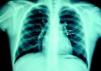

At the age of 11, he was referred to the pediatric cardiology department due to angina and exertional dyspnea of one month's evolution. The chest X-ray revealed a round area of calcification in the upper left portion of the cardiac silhouette (Fig. 1). There were no alterations on the electrocardiogram (ECG). Echocardiography showed ectasia of the left coronary artery of 4 and 5mm in the proximal and distal segments, respectively, with no wall motion abnormalities or mitral regurgitation. During nuclear perfusion scan with exercise, the patient reported chest discomfort at peak exercise, when the ECG showed ST-segment depression in II, III, aVF, V5 and V6. The nuclear perfusion scan during exercise showed severe hypoperfusion in the apex and the anteroseptal, apical-septal, and anteroapical segments and moderate hypoperfusion in the mid and basal segments of the anterior, inferior and inferoseptal walls, corresponding to the territories of the left anterior descending (LAD) artery and the right coronary artery (RCA), the alterations being reversed at rest. Cardiac catheterization revealed occlusion of the proximal segment of the LAD downstream of the calcified aneurysm, with retrograde filling by collateral circulation from the proximal branches of the left coronary artery (Fig. 2), and of the proximal RCA, with retrograde filling by collateral circulation from the left coronary artery (Fig. 3). Left ventriculography demonstrated good function, with no ventricular aneurysmal alterations.

(A) Left coronary angiography: left anterior descending artery occluded distal to the calcified aneurysm (arrow). (B) Left coronary angiography showing calcified aneurysm (arrows). (C) Left coronary angiography: occluded left anterior descending artery with late retrograde filling by collaterals from the left coronary circulation (arrows).